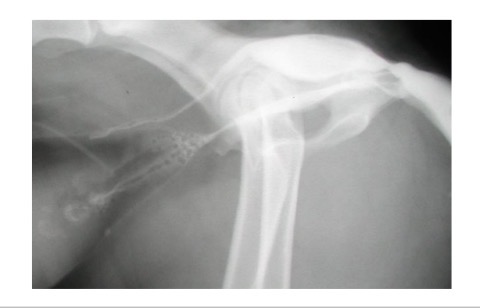

Radiography - plain, positive contrast urethrography

What can positive contrast radiography detect in urethral obstruction

Displaced bladder, radiolucent calculi, soft tissue lesions